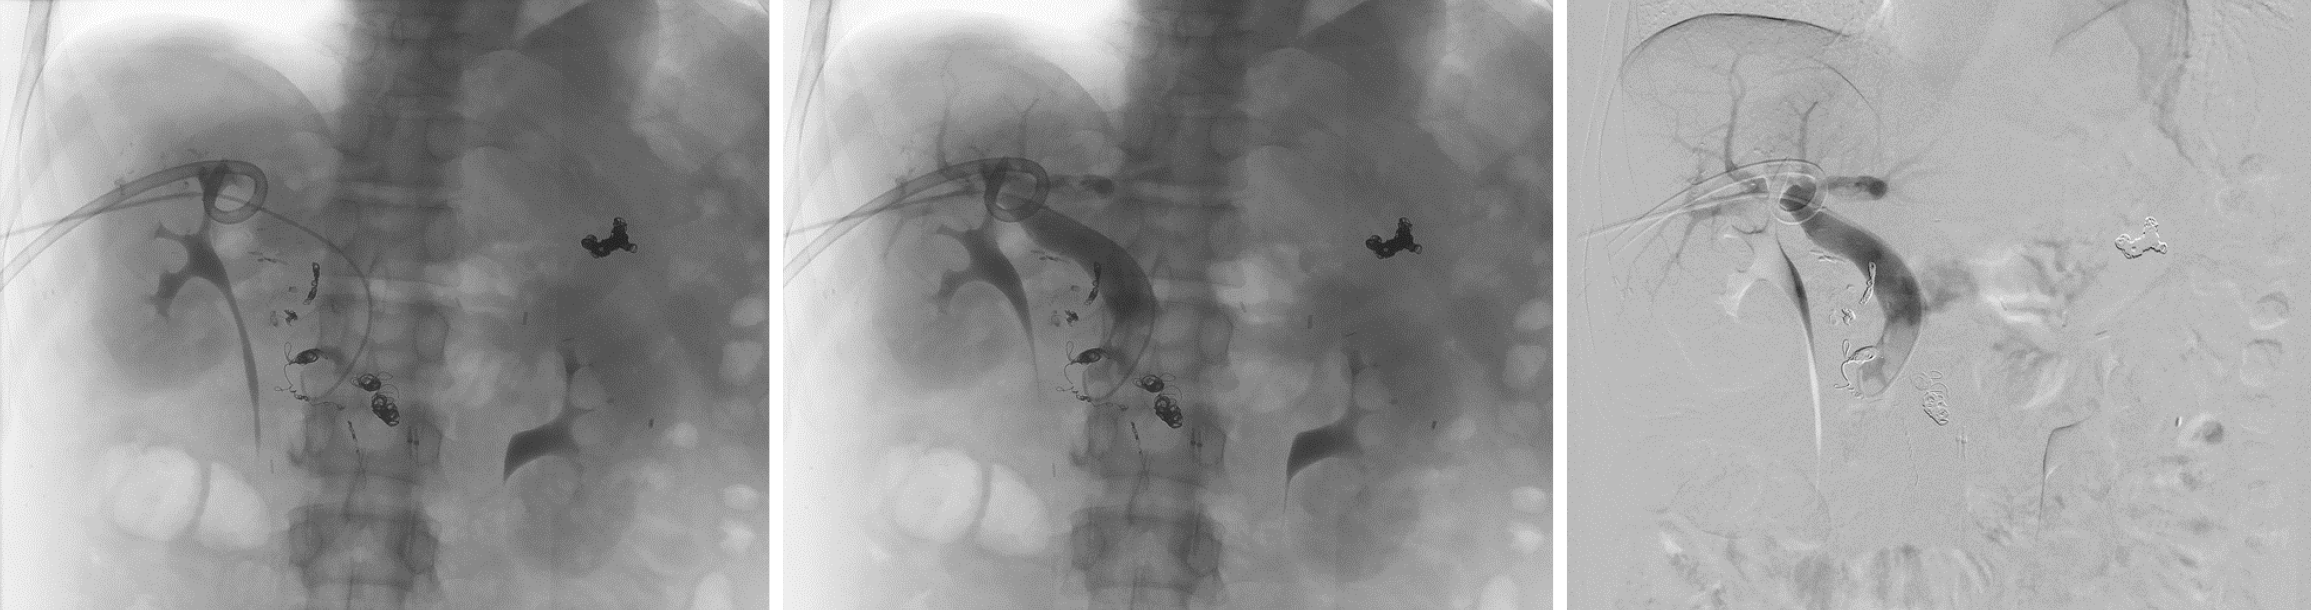

Figure 3 Interventional radiology.

Embolization with 33% glue and 4 micro-coils at draining vein of duodenal varix for hemostasis.